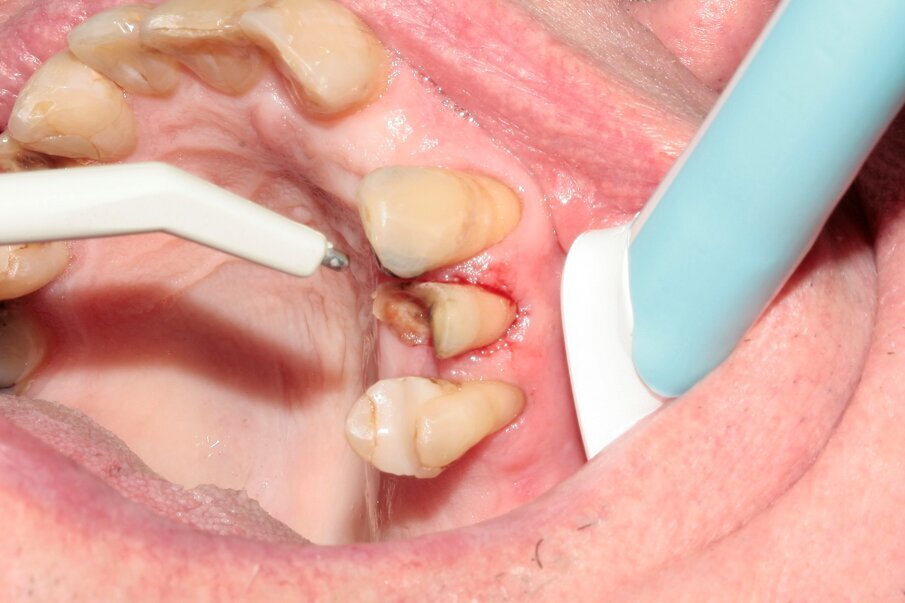

Figs. 13–15: The remains of the root were removed with the help of diamond tweezers.

By means of a gentle extraction technique, we managed to preserve the interradicular septum. Luxator P4, with its extremely sharp dual-edge blade, was used at the beginning, followed by Luxator P1 once some space had been created. Although the blades of these sophisticated instruments are reinforced with a titanium coating, they should only be used to cut the periodontal ligament and never to elevate the tooth.